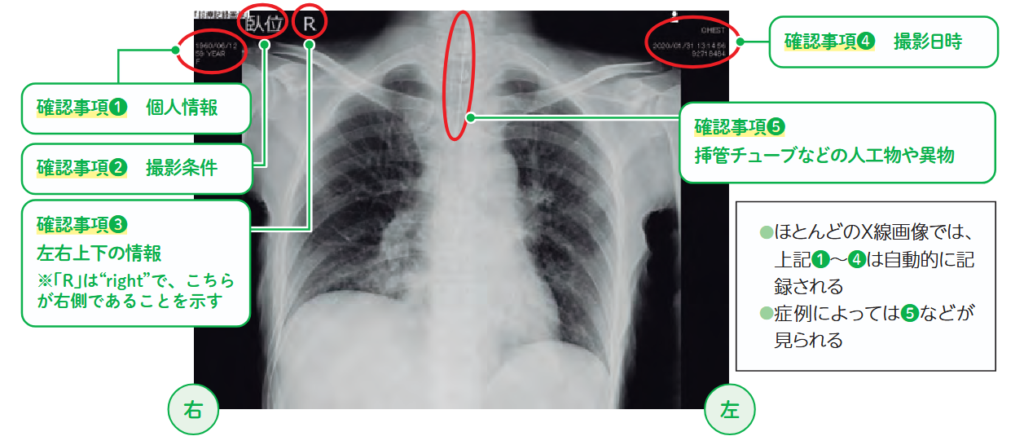

X線画像を閲覧する前の一般的注意事項

便利なことと危険なこと、これらが常に併存しているのは、画像検査も同じです。X線画像を閲覧するときの一般的な確認事項は表1の5つです。いずれも、確認が疎(おろそ)かになると医療過誤に直結するので注意が必要です。

表1 X線画像の一般的な確認事項

①氏名の確認

②撮影条件の確認

③左右上下の確認

④撮影日時の確認

⑤ラインやチューブの確認

「危険なこと」を避けるために画像を見ないというのも1つの見識かもしれませんが、X線画像の知識が増えると自然と危険回避の方法が身につきます。これは、採血や導尿などの日常の看護業務にも言えることかもしれません。患者さんにとって有益なことは、学びを深めて危険を回避しながら実践できるようになることのほうが、理にかなっているように思います。

表1「確認事項」のうち、①~④は基本的な確認事項です。患者さんによっては⑤が見られる場合があります。日常的に患者さんと接していますので、「気管挿管されている」「PICC*¹が入っている」「胃管が留置されている」といったことは、事前情報によって確認が比較的容易なはずです。図1に、表1に沿った大まかな観察部位を示しました。

*1【PICC】peripherally inserted central catheter:末梢挿入型中心静脈カテーテル